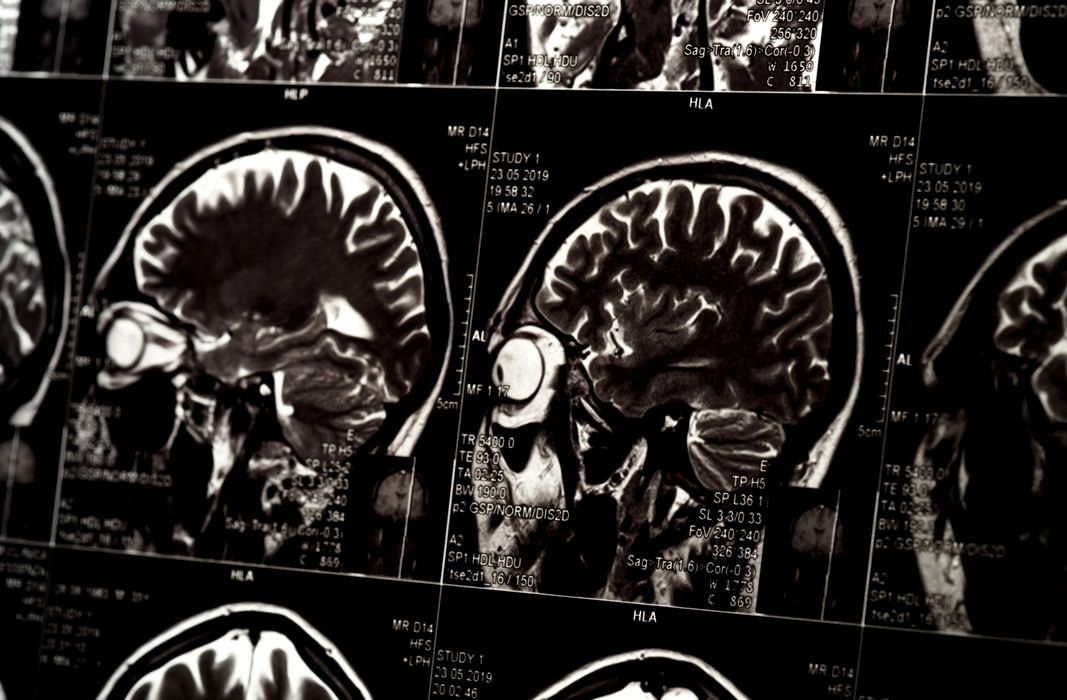

Ce au descoperit cercetătorii atunci când au scanat creierul oamenilor cu ideologii autoritariste?

Persoanele care susțin ideologii autoritariste, indiferent de orientarea politică, prezintă, potrivit unui nou studiu, particularități cerebrale neobișnuite. Ce au descoperit cercetătorii când au scanat creierii autoritariștilor? Ce au văzut cercetătorii când au scanat creierii autoritariștilor? […]